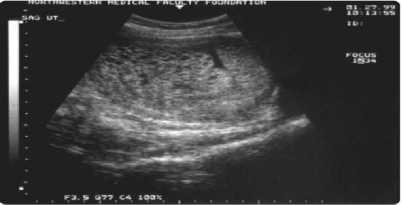

dalam darah. Kadar normal serum β-hCG adalah < 5 mIU/mL dalam darah bahkan bisa menyentuh angka 0 mIU/mL.7 Secara radiologis pasien PTG dapat dilakukan pemeriksaan USG pelvis untuk melihat apakah ada masa komplek yang disertai dengan adanya neovaskularisasi dan tampak seperti terdapat lubang-lubang pada plasenta dan biasanya tidak ditemukan keberadaan fetus (Gambar 1).6 Selain itu USG dapat menilai apakah ada metastase pada hati, ginjal dan daerah abdomen, CT-Scan dan MRI dapat menilai adanya metastase pada hati, otak, dan saluran gastrointestinal, dan foto toraks dapat dilakukan untuk menilai metastase pada paru-paru.8 Pemeriksaan histopatologi dapat dilakukan untuk mengetahui dengan pasti dari jenis PTG. Gambaran histopatologis dari mola hidatidosa komplit (Gambar 2) terdapat pembengkakan villi korionik serta hyperplasia cytotrophoblast dan syncytiotrophoblast yang menyebar, dan gambaran lain yang dapat dilihat adalah tidak adanya jaringan embrionik serta pembuluh darah pada villi. Gambaran histopatologis dari mola hidatidosa parsial (Gambar 3) terdapat pembengkakan villi korionik yang serta hyperplasia trophoblastic yang terfokus, selain itu juga terdapat jaringan embrionik, inklusi trofoblastik stromal dan adanya Scalloping of Chorionic Villi.1 Gambaran histopatologis dari mola invasif (Gambar 4) berupa perluasan jaringan molar, sampai menyelubungi trofoblas yang mengalami hyperplasia, sampai ke myometrium.6 Gambaran histopatologi dari choriocarcinoma (Gambar 5) adalah tumor malignant tanpa villi korionik, synsiotrofoblas dan sitotrofoblas yang abnormal,nekrosis, dan hemorrhage.9 Gambaran histopatologis PSTT (Gambar 6) adalah adanya mononuclear sel trofoblas tanpa adanya villi korionik pada lembaran antara serabut myometrial.6

Gambar 1. Gambaran Ultrasonografi pelvis dari mola hidatidosa